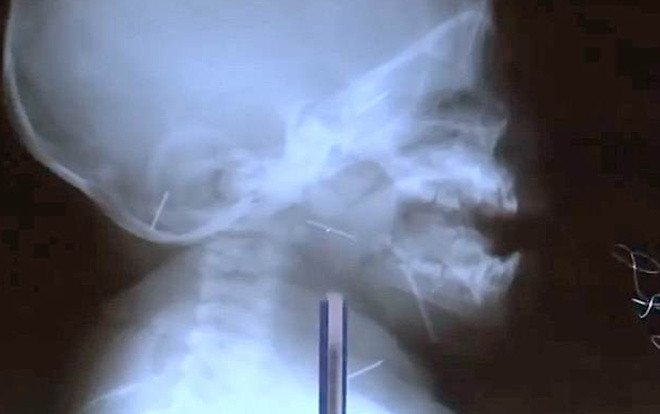

Mẹ của bé Mudassir Karimov là người đầu tiên phát hiện ra một cây kim trong nướu của con trai và sau khi đưa bé đến bệnh viện các bác sĩ phát hiện thêm nhiều chiếc kim nữa trong hộp sọ, mũi, chân, cổ và ngực bé nhờ vào ảnh chụp X-quang.

Theo các bác sĩ, cậu bé không thể tự mình nuốt phải kim. Gia đình em nghi rằng, người thân nào đó hoặc bảo mẫu có thể đã đưa kim vào cơ thể cậu bé để trừ tà ma.